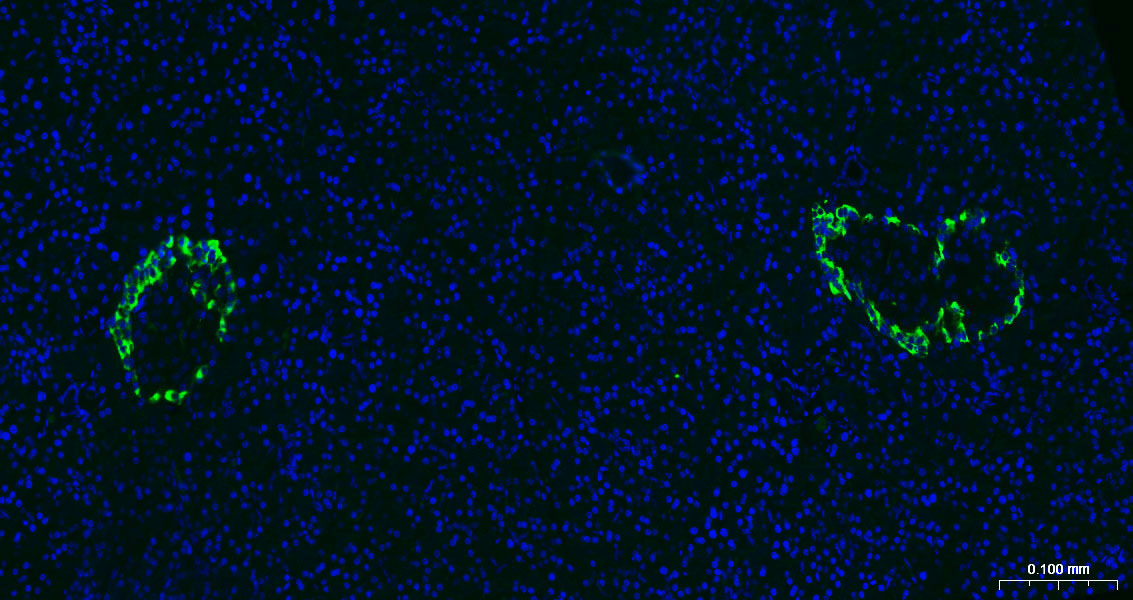

Paraformaldehyde-fixed, paraffin embedded Rat Pancreas; Antigen retrieval by boiling in sodium citrate buffer (pH6.0) for 15 min; The section was incubated with Chromogranin B Polyclonal Antibody, Unconjugated (bs-0543R) at 1:200 overnight at 4°C. Followed by conjugated Goat Anti-Rabbit IgG antibody (green, bs-0295G-BF488), DAPI (blue, C02-04002) was used to stain the cell nuclei.